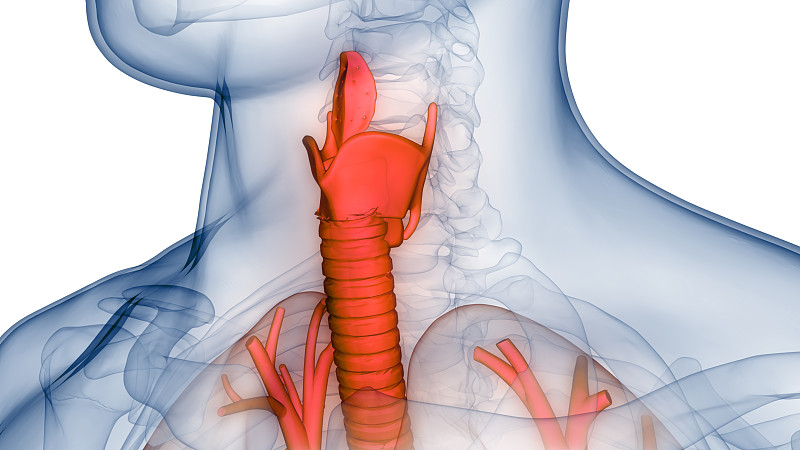

人体呼吸系统肺解剖学详情

JPG